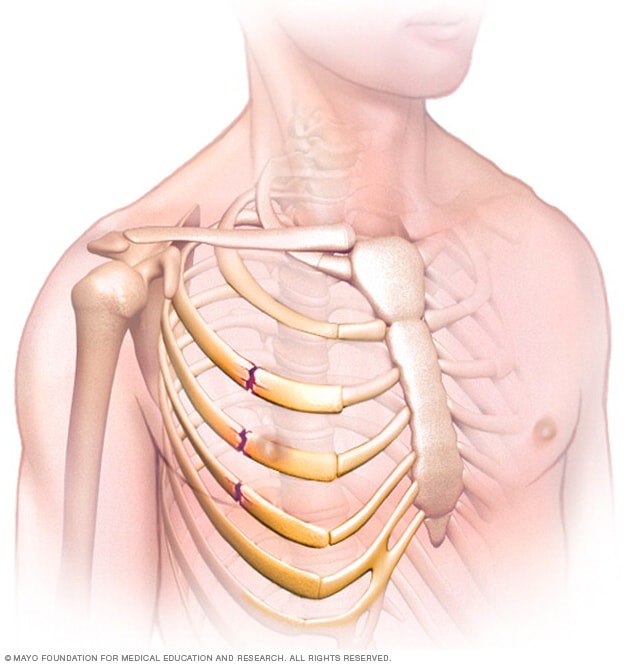

A broken rib typically causes sharp pain. To diagnose a rib injury, it’s best to see a medical professional who can look at your injuries with professional tools and technology. You may also feel or hear a crack or pop when the.

Sometimes, you may be able to feel a break in your rib by rubbing your finger over the rib. If you have a tender area on your ribs that hurts with every breath, you may have a broken rib. If you heard cracking during the injury or you hear or feel cracking when you move or.

Take slow, deep breaths and cough regularly to expand your lungs, use an incentive spirometer if asked to do so, get up and move around when you’re not sleeping,. When visiting your doctor, they will most likely be able to diagnose your injury simply by pushing on your chest and doing a physical exam. The pain you feel with a broken rib typically occurs or even worsens when you: